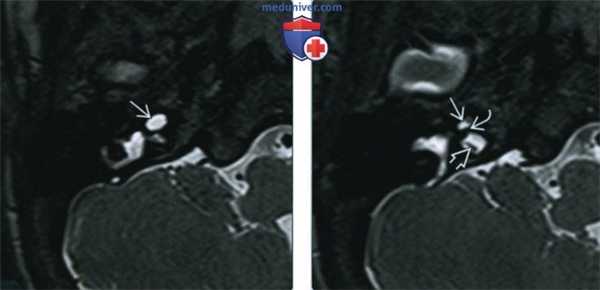

(Слева) На рисунке в аксиальной плоскости показаны признаки аплазии улитки, включая уменьшение внутреннего слухового канала (ВСК) с отсутствием улитковою нерва, улитки; с мальформацией преддверия и полукружного канала, уплощением переднею колена ЧH VII.

(Справа) При аксиальной МРТ SPACE у четырехмесячной девочки с врожденной НСТУ отсутствует улитка. Определяется глобулярная аномалия преддверия и горизонтального полукружного канала. В коротком и узком внутреннем слуховом канале находятся преддверный и лицевой нервы. Улитковый нерв не визуализируется.

1. КТ при аплазии улитки:

• КТ в костном окне:

о Улитка: отсутствует с одной или с обеих сторон

о Канал улиткового нерва: отсутствует

о Мыс улитки: гипоплазия, уплощение

о Преддверие и ПКК: мальформация, шаровидная форма, расширение или гипоплазия (часто)

о Водопровод преддверия: обычно норма

о Канал лицевого нерва: аномальный тупой угол переднего колена

о ВСК: обычно гипоплазия

о Среднее ухо: нормальный размер

о Слуховые косточки: норма или мальформация стремечка

о Овальное окно: норма или стеноз/атрезия

о Круглое окно: атрезия

2. МРТ при аплазии улитки:

• Т2 ВИ:

о Улитка и улитковый нерв: отсутствуют

о Преддверие и ПКК: различные нарушения